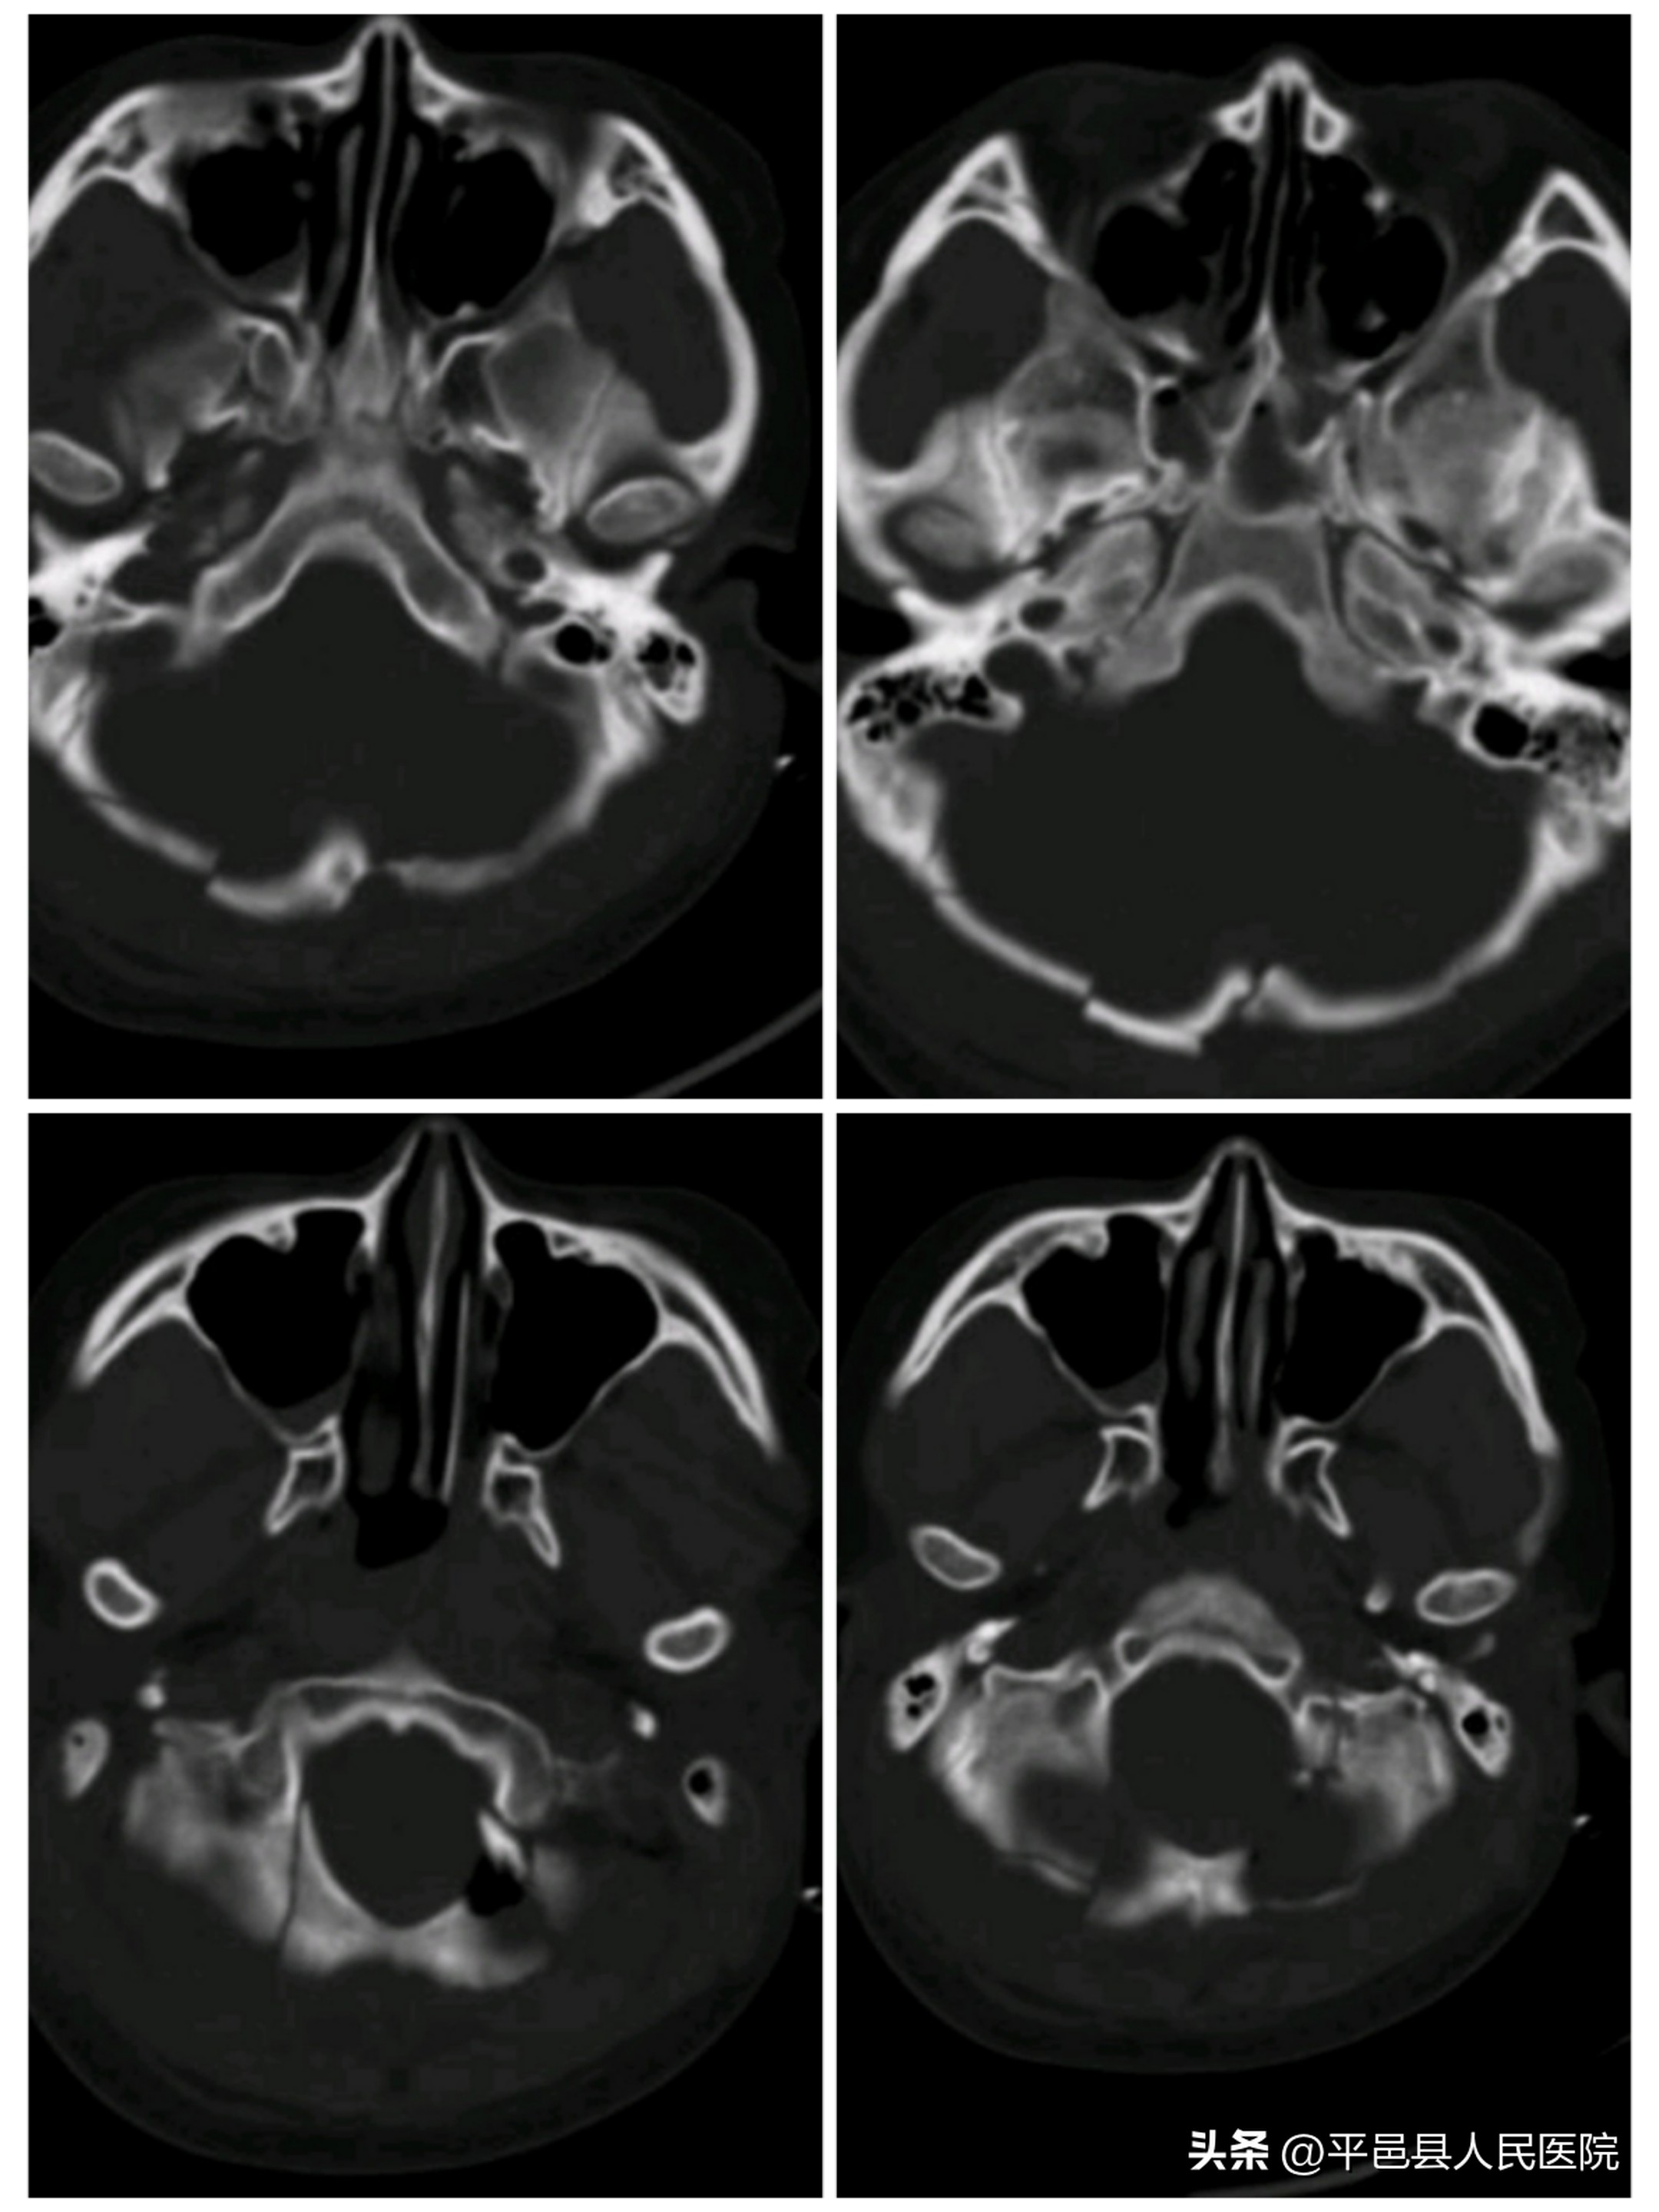

小脑挫裂伤并脑内血肿压迫脑干

枕骨粉碎性骨折累及枕骨大孔

随后多发性小脑挫裂伤、小脑血肿、枕骨凹陷、粉碎性骨折由神经外科二病区紧急行小脑血肿清除、枕骨粉碎骨折清除减压手术,同时给予输血、补液纠正休克,手术顺利完成。术后转入神经外科二病区继续治疗额颞叶多发大脑挫裂伤、硬脑膜下血肿、硬膜外血肿。